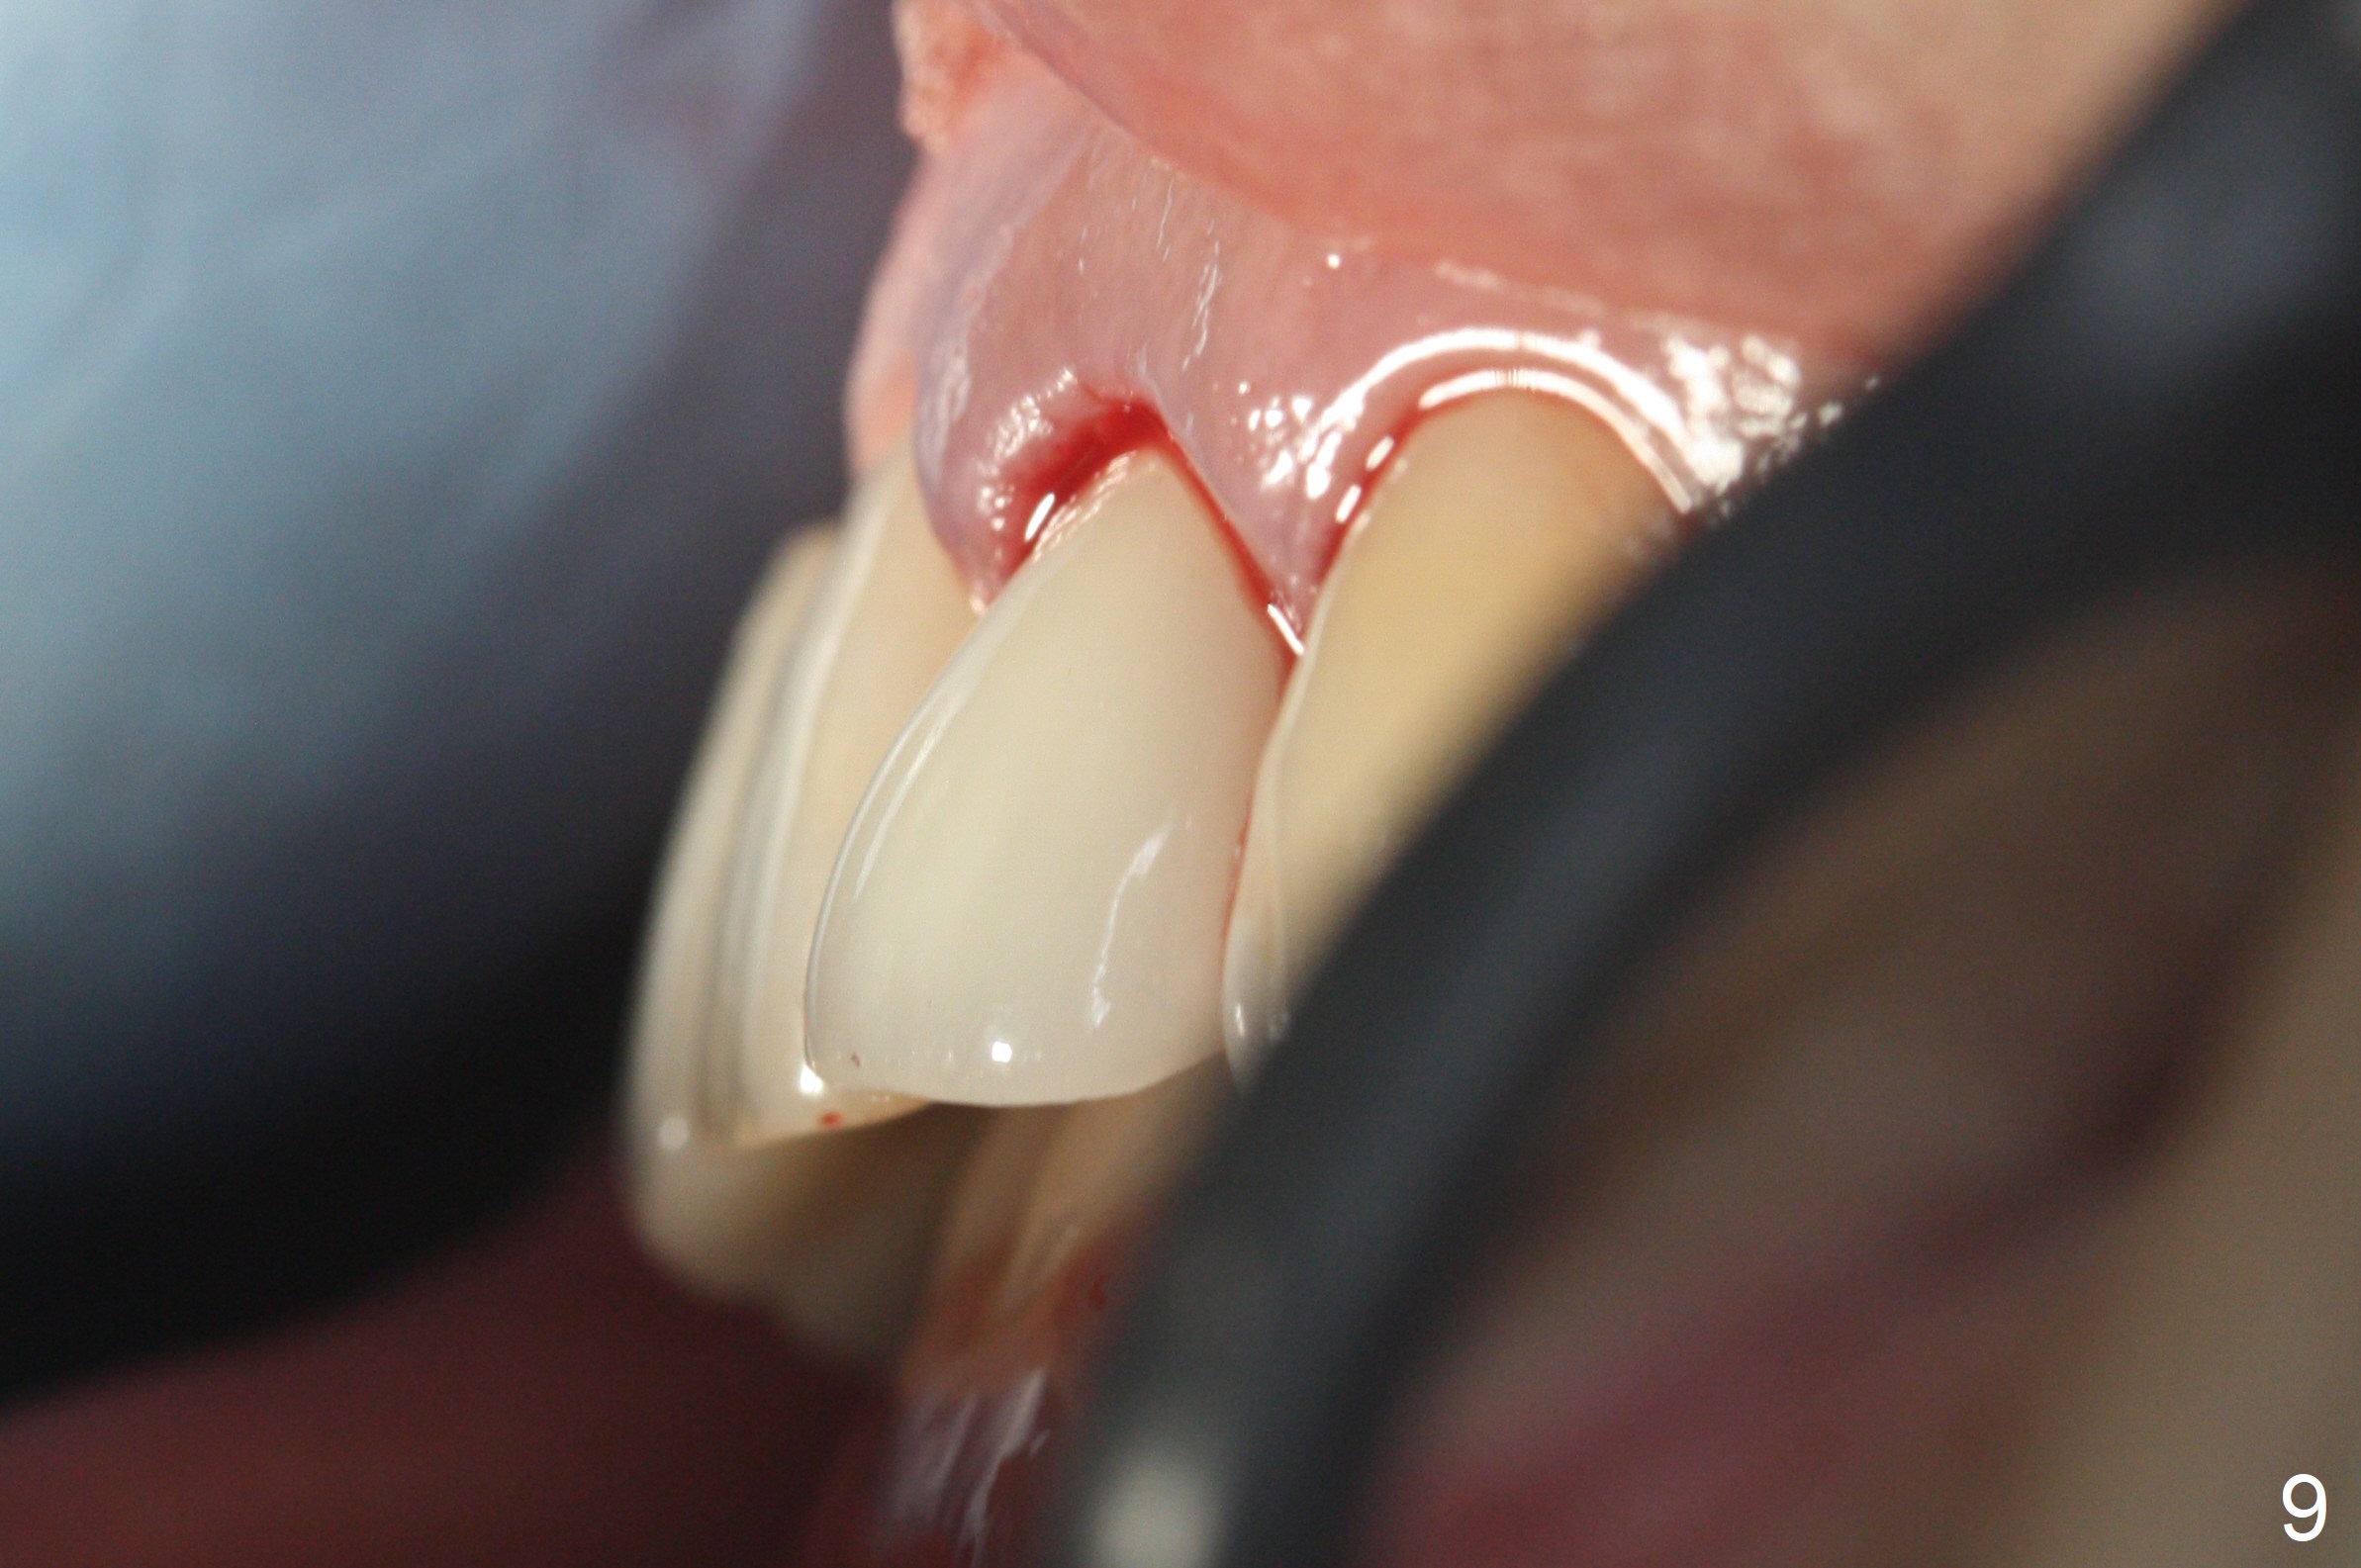

When the patient returns, the crown at #10 has displaced incisally (Fig.1,2 arrow). The initial depth is 15 mm (Fig.3, palatal gingival margin). After a 3.8x12 mm SM implant is placed (Fig.4), allograft is packed in the peri-implant space (*, as compared to Fig.3) and a 3.9x4(3) mm abutment is placed (A). More allograft is placed in the peri-abutment space (Fig.6 *). The existing crown (Fig.4,5 C) is hollowed, relined (R) and used as an immediate provisional (Fig.7-9). The patient is pleased with the appearance of the apically-repositioned provisional (Fig.7 arrow). She returns for impression 3.5 months postop (Fig.10). After change of abutment to 3.9x4(4.5) mm and new provisional, impression is retaken 5 months postop (Fig.11,12). It appears that the implant is palatally placed and a little large for the site (Fig.11 (B: buccal); Fig.12 (^: thin layer of the palatal plate)). If an angled abutment were used, a screw-retained crown might have been feasible. Due to the new provisional, the gingiva looks healthy when a permanent crown is cemented (Fig.13).